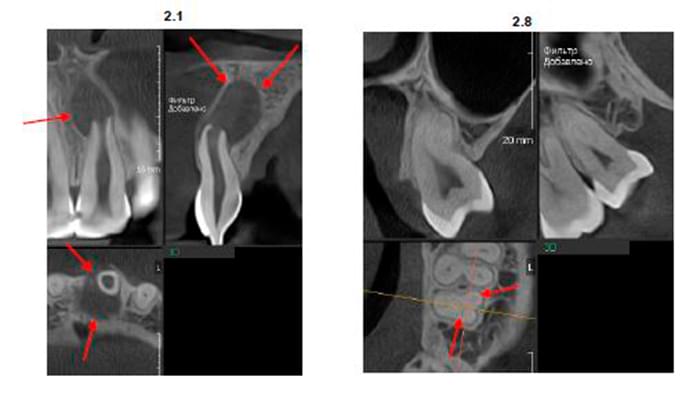

CBCT Maxilofaciální diagnostika

Grafický popis problémových oblastí